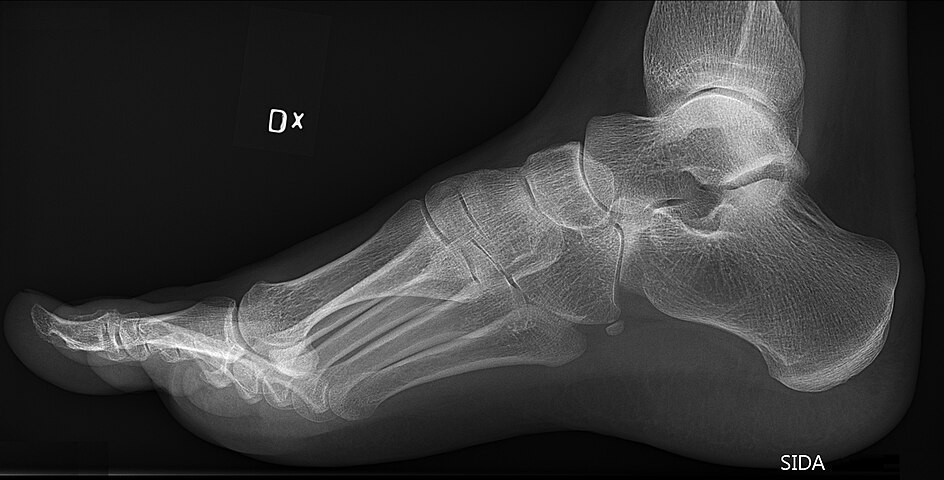

Some people have more bones in their feet than others. Actually, it’s not all that uncommon to have extra bones in the feet. These extra bones are called accessory bones. The navicular bone, one of the small bones located at the instep or arch of the middle of the foot, is an example of an extra bone people are born with. It’s called the accessory navicular bone. (See x-ray.) During the maturation process, the navicular and the accessory navicular never fuse into one solid bone but remain connected by fibrous tissue or cartilage. It is estimated that 4-14% of the population is born with an accessory navicular bone.

X-rays are usually ordered to confirm the diagnosis. If there is ongoing pain or inflammation, an MRI or other advanced imaging tests may be used to further evaluate the condition.

Figure 1. Bony anatomy of the foot – relationship of mid-foot bones to metatarsals and proximal tarsal bones |

Figure 6. Medial tubercle of navicular |

Older patients (14–24 years) may present with localised pain, medial navicular prominence or tenderness medially. Diagnosis can be confirmed on plain X-ray or with MRI if uncertainty persists. Although the underlying anatomy will have been present long term, there must have been occasional instances of overload, placing stress on the synostosis between the two navicular fragments and causing pain.